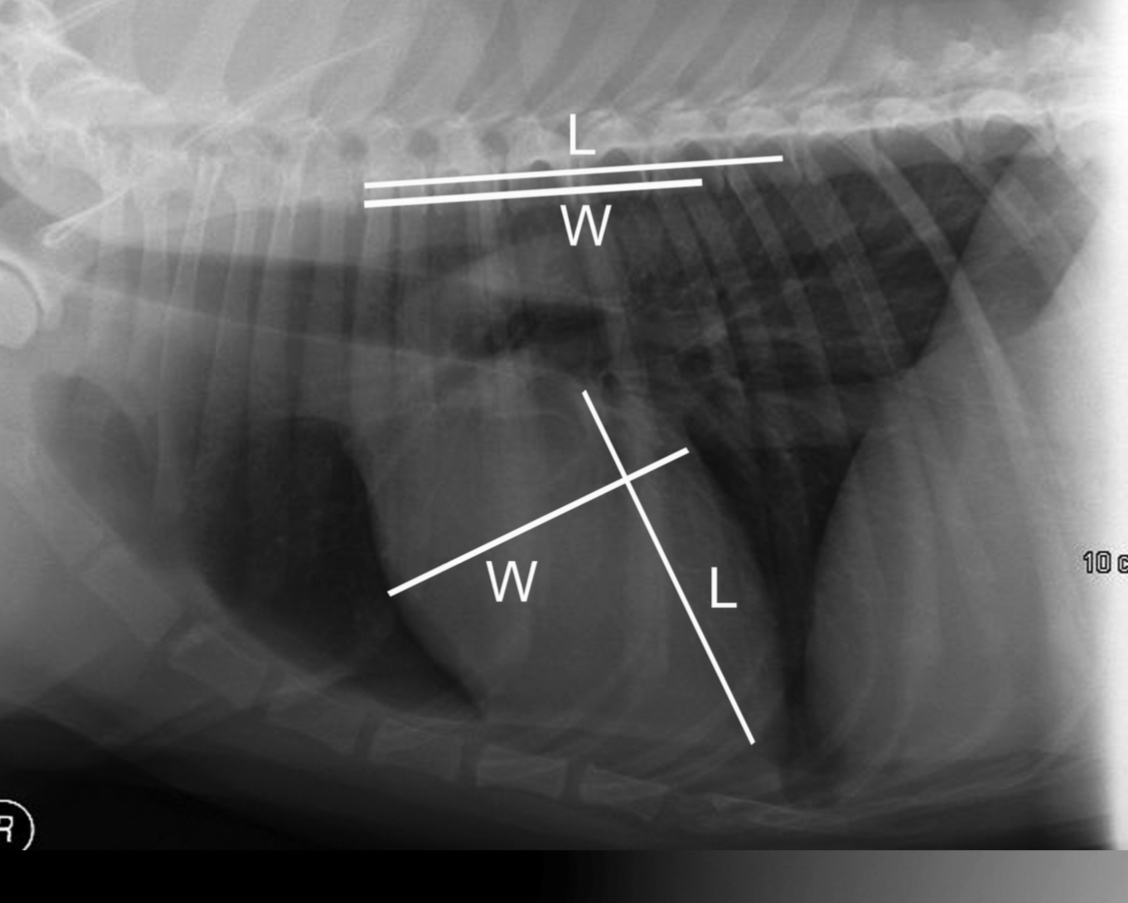

How do we measure heart size on rads

Vertebral heart score

-put the heart width and length along the vertebrae starting at T4 = cumulative sum of vertebra between length and with = vertebral heart score

3 features LVE on lateral

-tall heart (>2/3 DV diameter)

-dorsal displacement of trachea (almost parallel to spine)

-straightening of cd. border of heart

What part of the heart is enlarged?

LVE (technically LAE too) - prof used the same photo for both but outlined different features

3 features of LVE VD

-elongation of cardiac silhouette

-deviation of apex to the left

-bulge at 3-5 o’clock

LVE